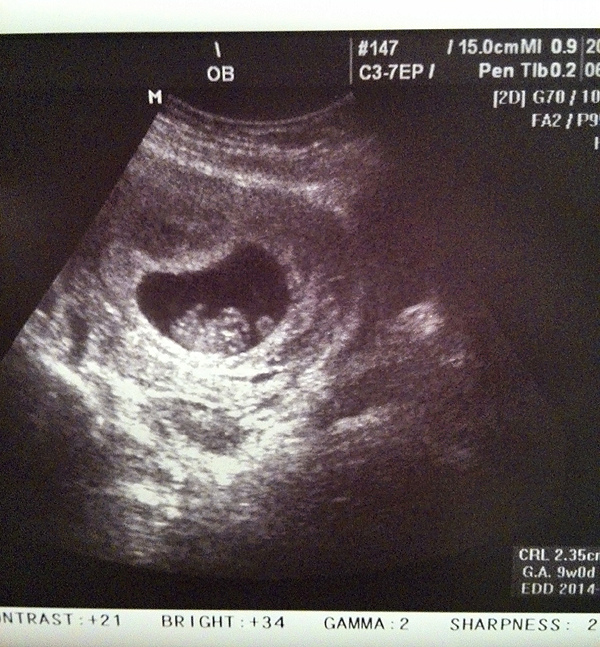

2014 / 02 / 26

這一天肚子裡的寶貝已經有九週了,也照到一閃一閃的心跳,像星星一樣

我的週數是靠照超音波檢查判定,本以為算起來應該八週而已

結果一照超音波,醫生說已經有九週了,還說他已經是個小肉糰了

所以那天從醫院回家後,我跟威猛哥就開始叫肚子裡的寶貝為小肉糰XDDD